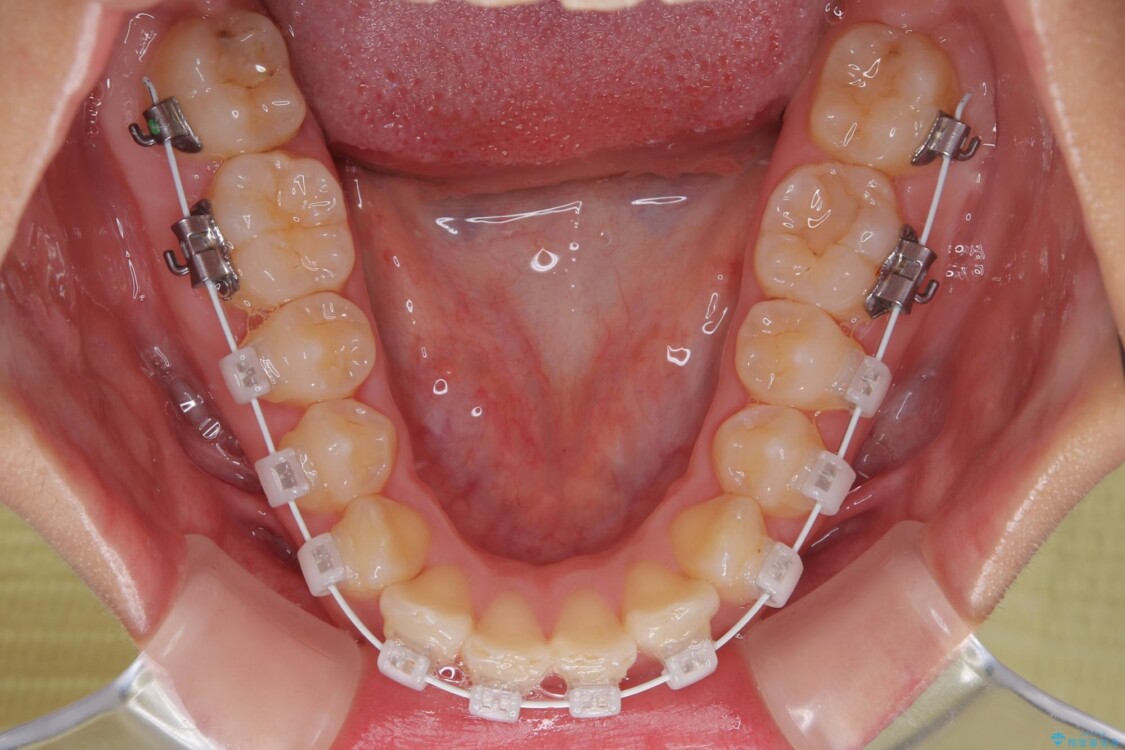

治療途中

• 目立ちにくい表側装置で1年完了!狭いアーチを側方拡大し前歯のデコボコを整えた症例 治療途中画像